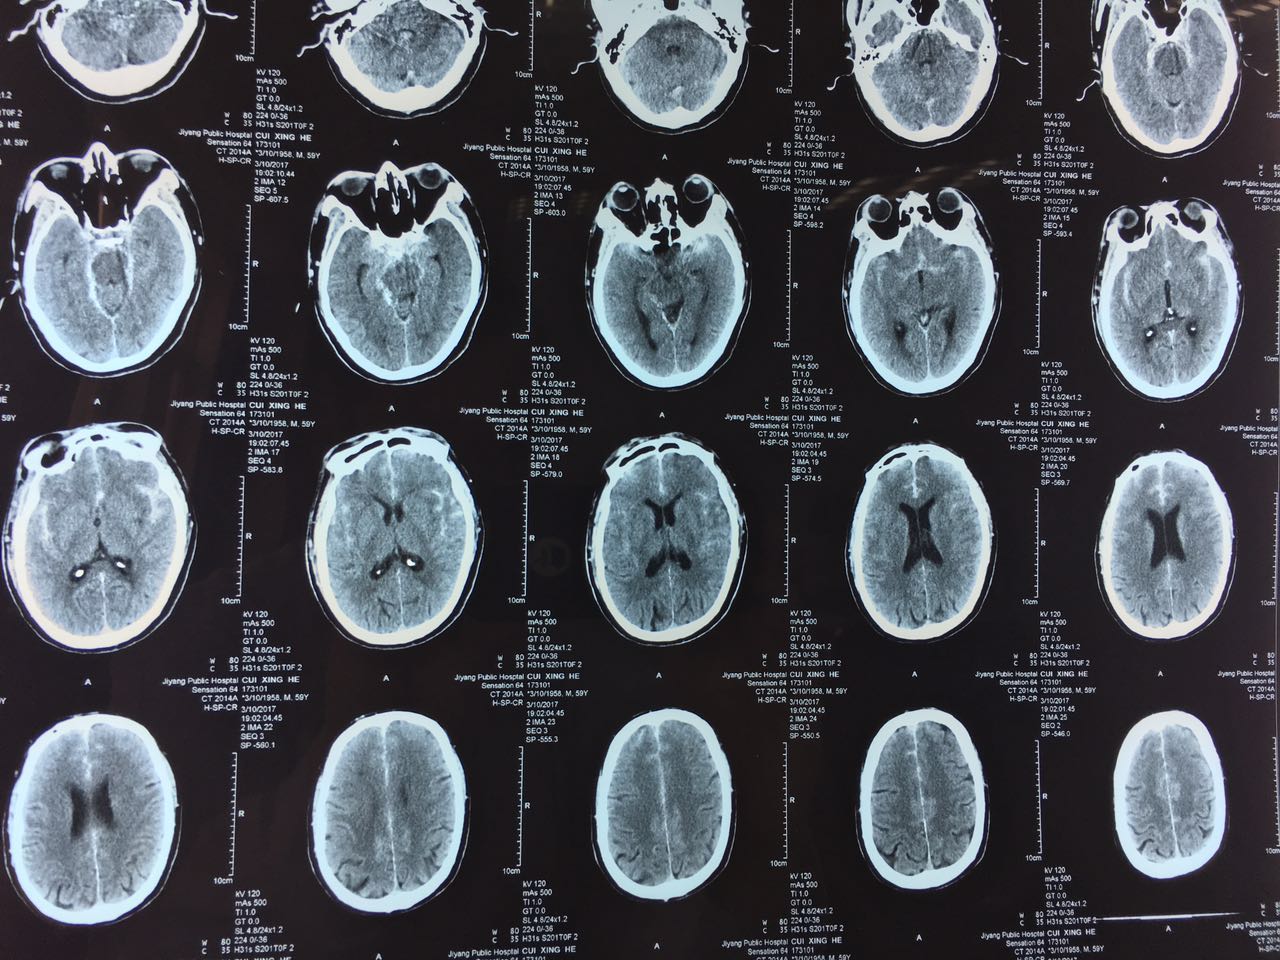

患者王某某,因“突发头痛2小时”来我院就诊,入院后急查颅脑CT示蛛网膜下腔出血。高磊主任急查房并阅片,考虑病人出血部位以双侧外侧裂、皮层下沟池为主,左侧为主,病人四叠体池、桥池、环池周围血量很少,为次级血管动脉瘤可能性较大。遂行颅脑MRA检查初步筛查,未见动脉瘤。考虑病人急性期血管痉挛,仍应继续排查动脉瘤,2天后为其行全脑血管造影术,造影示:胼缘动脉与大脑前动脉交界处动脉瘤。胼缘动脉与大脑前动脉交界处动脉瘤在临床上极其少见,手术风险极大,此前此类病人只能开颅动脉瘤手术夹闭,创伤大、预后差、并发症多。高主任组织科室技术骨干积极进行术前讨论,最终决定为患者实施全身麻醉+支架辅助下动脉瘤微弹簧圈栓塞术。手术顺利完成,术后患者恢复良好。